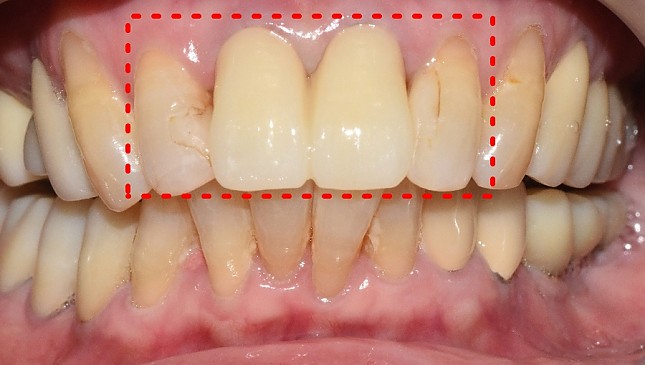

잇몸재생교정 치료 전후사진

잇몸 전체가 무너져 동시다발적으로 죽어가던 치아들을 한꺼번에 살려 냅니다.